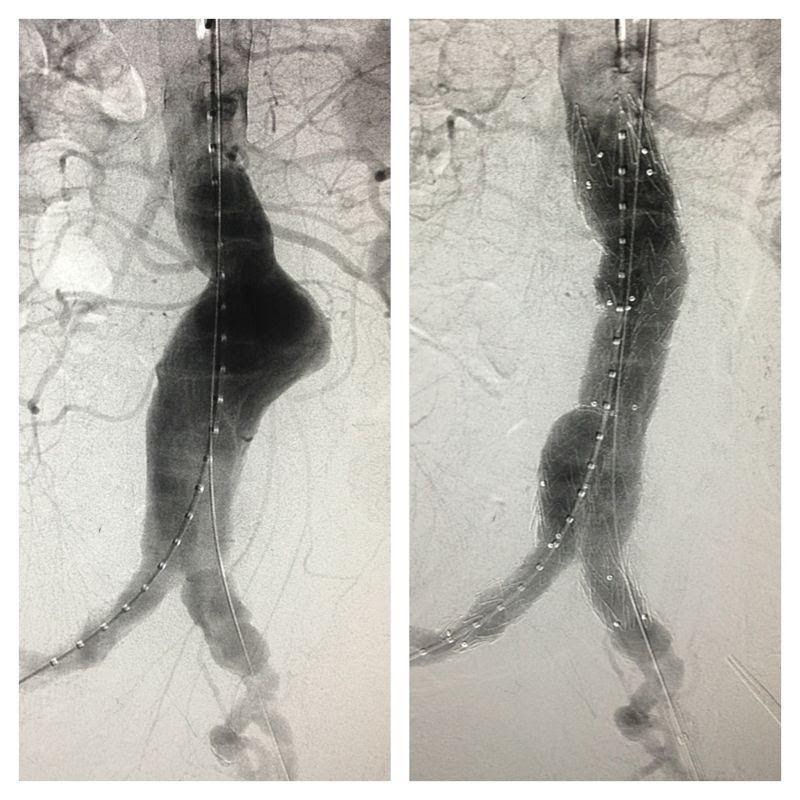

At the other hand EVAR procedure (Figure 7,8) involves access to femoral artery by cut down or percutaneous method, wiring into ascending aorta, tracking delivery device up into the aneurysm, stent graft deployment and then repairing the access femoral artery. The procedure avoided cross clamping of aorta and reduces blood loss intra-operatively. This help to maintain the hemodynamic during aneurysm repair, and hence reducing the stress to cardio-vascular system and to the patient as a whole.

Figure 8: Angiographic picture of AAA, pre & post

As a minimally invasive therapy, EVAR greatly reduces the peri-operative mortality to around 2% and below. More importantly it reduces the ICU stay, reduces prolonged ventilation need, reduces blood transfusion and return the patient to normal life as soon as one can imagine. Its uses in ruptured or leaking AAA also improved patient’s survival rate and reduces the morbidity, even though the operative setting is different.